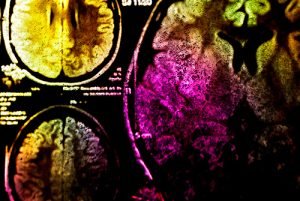

Рак мозга – тяжелая болезнь, лишающая человека возможности жить полноценной жизнью. Но израильская медицина уверенно идет в сторону полной победы над злокачественными новообразованиями. Благодаря современным медицинским технологиям и новаторским подходам лечение рака мозга в Израиле проходит максимально эффективно, данную патологию можно полностью устранить или же добиться длительной и стойкой ремиссии.

Лечение рака головного мозга в Израиле осуществляется с помощью современных эндоскопических техник в нейрохирургии, а также безоперационных методов, таких как стереотаксическая радиохирургия.